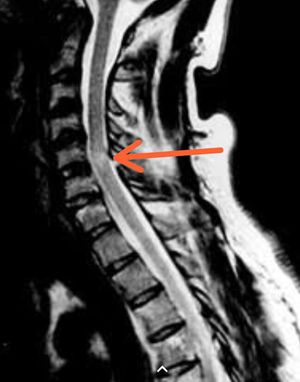

Brown sequard syndrome hemisection of spinal cord but uncommon brown sequard plus syndrome more common